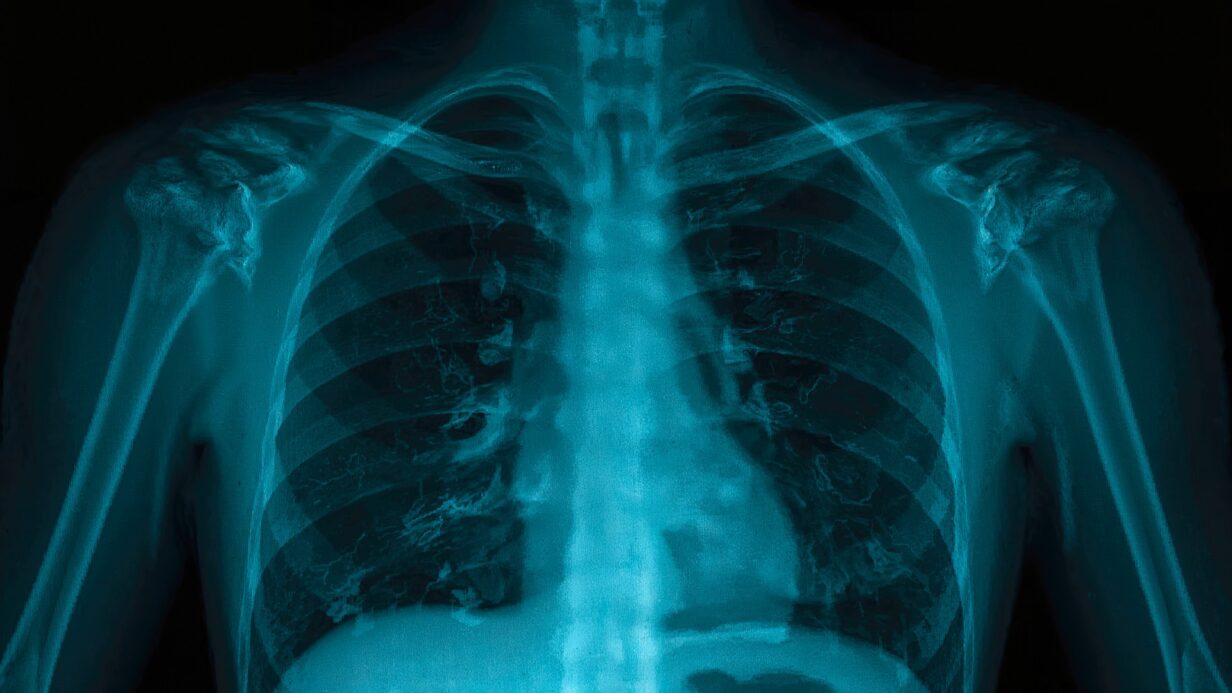

Un article publié dans la Revue Radiology met en lumière l’essor fulgurant de l’intelligence artificielle en imagerie thoracique.

• Interprétation assistée des radiographies et TDM thoraciques

• Détection automatisée des nodules pulmonaires, embolies ou pneumothorax

• Dépistage opportuniste des maladies non ciblées